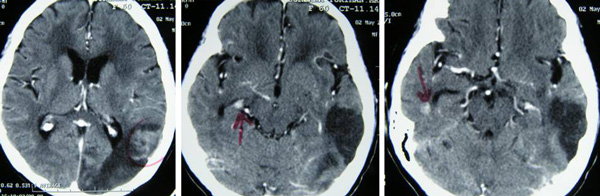

A CT scan done on 21 February 2013 indicated the following:

- Multiple pulmonary nodules in both lower lobes. Right pleural effusion and enhancing right pleural nodules.

- Bilaateral heterogeneously enhancing renal masses in upper pole measuring 7.3 x 6.6 cm (right) and 7.0 x 8.1 cm (left).

- Right lobe liver with ill defined lesion in segment IV of liver suggestive of local infiltration.

- Multiple enhancing peritoneal nodules in right subhepatic space.

- Enlarge retrocrural lymphadenopathy and multiple subcentimeter paraaortic and aortocaval nodes. Mild to moderate ascites.

Impression: Bilateral renal masses likely renal cell carcinoma with local infiltration and lung pleural and peritoneal metastases.

After the CT scan KC was asked to go home and nothing was done. There was no medication either. No satisfied, KC went to consult an oncologist at a private hospital. Another CT scan was done on 26 March 2013. The results indicated: